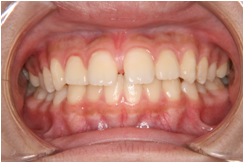

K:はい。代表的なものに「交叉咬合」と「埋伏歯」と呼ばれるものがあります。まず、「交叉咬合」とは、噛み合わせが左右にずれていて、下の奥歯が上の奥歯の外側にある状態です。(図1)

N:左は下の歯が外(頬)側に出ているのに、右は上の歯が外(頬)側に出ていて、雑巾を絞ったように左右の歯がねじれているようですね。何となく素人目にも健康状良くないというのは分かりますが、どのようなことを引き起こすのですか?